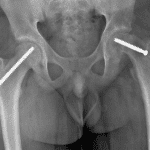

Age: 12

Sex: Male

Indication: Left hip pain

- Abnormal widening and lucency of the left proximal femoral physis

- Left hip is located

- Slipped capital femoral epiphysis (SCFE)

Abnormal widening and lucency of the left proximal femoral physis, concerning for slipped capital femoral epiphysis (SCFE). Recommend frog-leg lateral view of the hips for further evaluation.

Left hip is located.